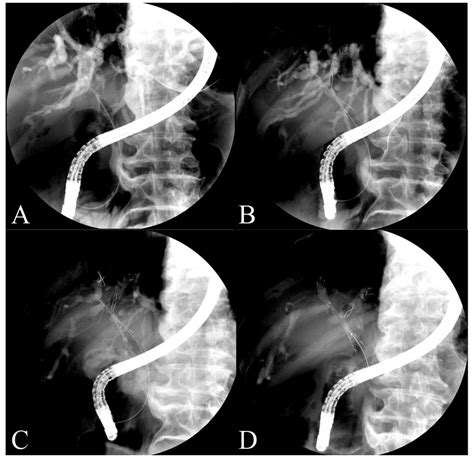

These devices are primarily inserted via a procedure known as Endoscopic Retrograde Cholangiopancreatography (ERCP). During this minimally invasive procedure, a gastroenterologist uses an endoscope—a flexible, lighted tube with a camera—to navigate through the esophagus and stomach into the small intestine, reaching the opening of the bile duct to deploy the stent.

• Imaging: Using fluoroscopy (real-time X-ray), the doctor identifies the exact location of the blockage.

• Deployment: Once the location is identified, the stent is advanced through the endoscope and expanded within the narrowed area of the bile duct.